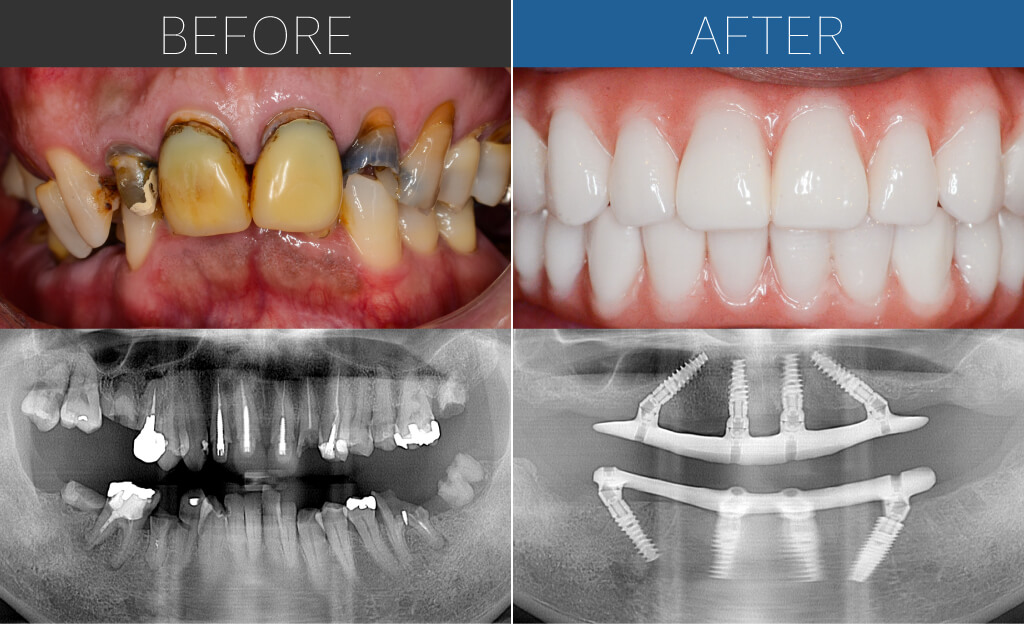

– Upper:All-on-4 + Zygoma

– Lower:All-on-4

Age:50s

| 主訴 | オールオン4を知り、「人前で思い切り笑えるようになりたい!」と思い来院。 |

| 治療内容 | 上顎は左側のザイゴマインプラントを含めて5本のインプラントによるオールオン4。下顎は基本的な4本埋入によるオールオン4。上下ともに即時荷重により手術当日に仮歯を固定。 |